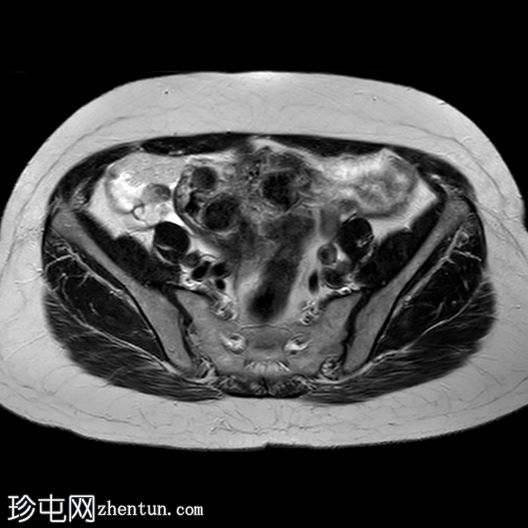

矢状位T1加权像

增强脂肪抑制像

4.jpg

增强扫描图像显示,与其他肌瘤相比,该病灶呈异质性强化,强化区域混杂,中心大片区域无强化(与T2加权像上的囊性区域相对应)。

病例讨论

在原有肌瘤内快速生长出一个体积较大、异质性且伴有囊性/坏死区域的病灶,高度怀疑为子宫平滑肌肉瘤。

遗憾的是,患者病情严重,无法进行进一步检查,因此无法通过病理学确诊。